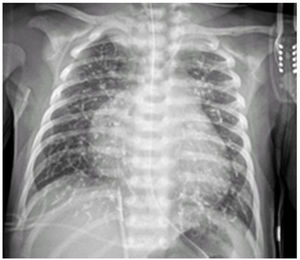

The newborn underwent an emergency coil embolization at 7 days post birth and a second embolization with cyanoacrylate (Glubran surgical glue) at 26 days post birth. Two hours after, he experienced an acute episode of crying, irritability, tachycardia and desaturation that required treatment with high-dose opiates. The follow-up radiograph showed radio-opaque material in the arteries compatible with pulmonary glue microembolism (Fig. 1). Milrinone had to be administered due to worsening of congestive heart failure and pulmonary hypertension.